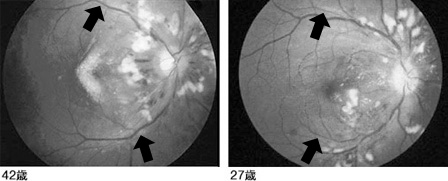

42歳と27歳の男性例

いずれも最大血圧が200を超えていた方の右眼底写真です。線のような白い濁りは小梗塞巣、点状の濁りは血管から汁が滲みだした滲出斑です。ですが、本当の問題は、うっかりすれば見落としてしまうまでに細い細動脈(矢印)なのです。